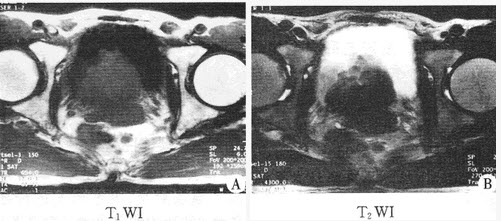

�����У�74�ꡣ��������������4���£�MRͼ�����£����п��ܵ�����ǣ���